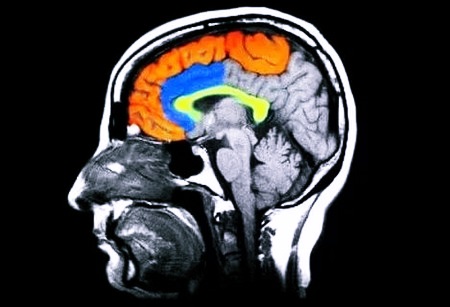

МРТ является неинвазивным обследованием с использованием высокочастотного магнитного поля, основанным на получении снимка с детальным изображением мозга. При МРТ головного мозга рентген не применяется. Данная методика помогает выявить опухоли, аневризмы, патологии в сосудистой и нервной системе.

Помимо этого, исследование помогает определить степень активности коры. МРТ головного мозга может проводиться с введением контрастного вещества и без него. Контраст увеличивает отличие между тканями, что дает возможность выявить даже мельчайшие патологии. Его используют достаточно редко из-за риска возникновения аллергических реакций.